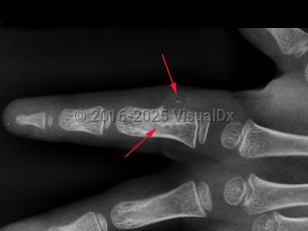

Periosteal chondroma in Child

A rare, benign cartilage tumor that typically occurs in the long tubular bones, but also commonly develops in the proximal humerus and short tubular bones of the hands. Periosteal chondroma develops on the surface of the bone, the periosteum, a membrane covering the bone. The tumor may develop in children and adults.

The precise cause is unknown. Patients with periosteal chondroma are typically asymptomatic. In some patients, symptoms include pain, swelling, palpable mass, or broken bone. Pain as a symptom may be an indication of a malignant tumor. In most cases, periosteal chondromas do not spread to other body parts, but they may continue to grow; some may become cancerous in adulthood.